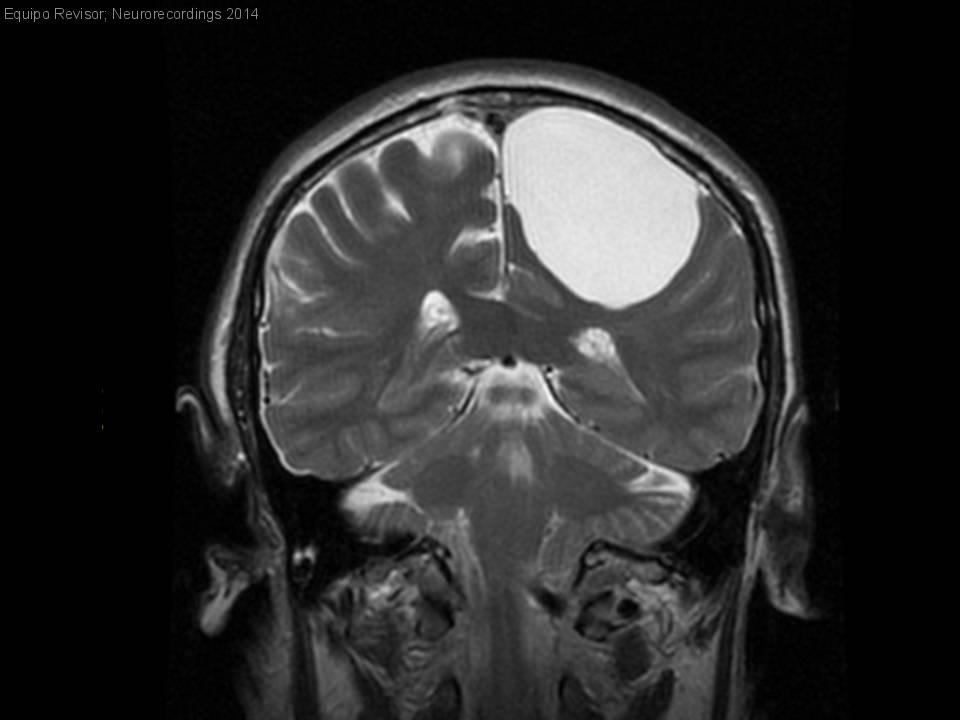

Quiste aracnoideo sintomático

Hombre | 70 años

Diagnóstico final: Quiste aracnoideo

Neurología: Epilepsia